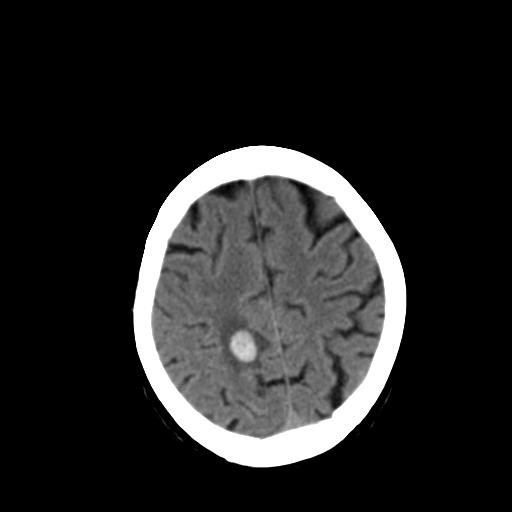

女,72岁,咳嗽一周余,突发右下肢无力二天。

pe:bp-140、80mmhg,精神可,伸舌居中,右上肢肌力正常,右下肢肌力0级,巴氏征+

来院做头颅+胸部ct平扫

遂加作增强:

这个病人首先是胸部病变的定位到底是肺内还是肺外。仔细观察块影位于胸膜下,与胸膜间有透亮带,且近端血管未见明显推移而是引流样改变,形态分叶,说明这个病灶位于肺内胸膜下。很可能是腺癌,腺癌最易致颅内高密度转移灶。局部胸膜有侵犯。

本例颅内见多发大小不等高密度灶,有强化及水肿;另外,胸锁关节层面可能是第四胸椎及右侧肋骨起始部骨质欠连续,椎旁软组织肿胀,建议调骨窗观察。

诊断:右下肺癌伴颅内、胸椎、肋骨转移可能性最大。

右侧胸膜间皮瘤,双肺大泡,颅内多发转移(右顶叶、左侧侧脑室前角放射冠区)并出血。

左侧额叶及右顶叶实质内病灶首先应该考虑是转移性肿瘤伴出血{结合胸部强化}.